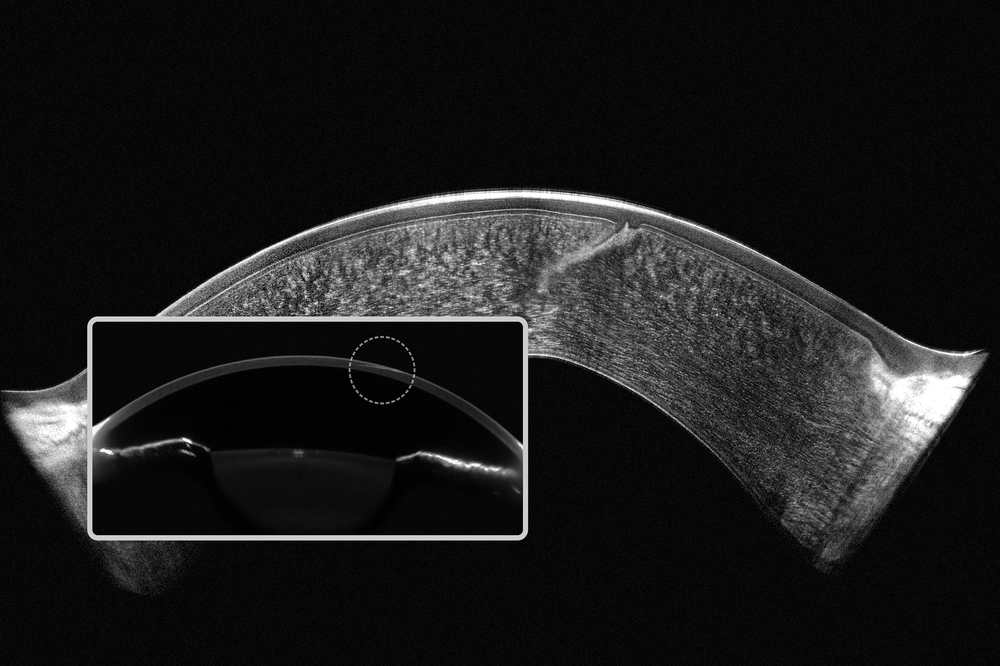

Door Scheimpflug-technologie en OCT te combineren ontstaat een volledig beeld: Scheimpflug toont lichtverstrooiende structuren in het voorste oogsegment met blauw licht, terwijl OCT ongeëvenaarde details geeft. Beide metingen worden gelijktijdig uitgevoerd op exact dezelfde locaties, wat directe en gedetailleerde visualisatie van alle afwijkingen mogelijk maakt.

- Scheimpflug toont verstrooiing;

- OCT geeft gedetailleerde structuren